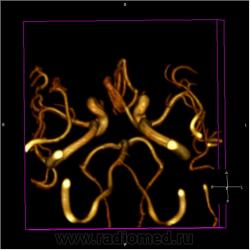

МР ангиография:

частично функционирующая аневризма

Иначе говоря, аневризма с хронической геморрагией, т.к. мы видим фракции крови различного возраста.

Я нарочито некорректно выразился, чтобы было понятнее. Естественно, подобных вольностей в заключение выносить нельзя. Я имел в виду аневризму и линейный участок в структуре геморрагии, который выглядит как сосуд, в частности при ангиографии. Извиняюсь, если кого-то сбил с толку.

По-моему, аневризма с пристеночными тромбами.

Постепенное пристеночное образование тромбов приводит к появлению типичного для аневризмы феномена -слоистости МР сигнала в полости аневризмы. Данная картина демонстрирует слоистый характер тромботических масс в полости аневризмы .Функционрирующая часть имеет низкий сигнал во всех режимах сканирования. Дополнительно-перифокальный отек.

А может более корректно интерпретировать как частично тромбированная аневризма... Уж коь речь идет о фракциях, ну то есть о тромбе по сути.... Ну и плюс перфокальный отек головного мозга (вероятнее цитотоксический+вазогенный).